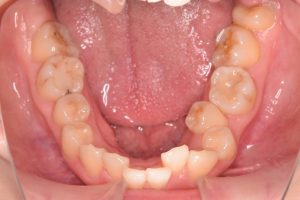

下あご

0000000012

0000000140